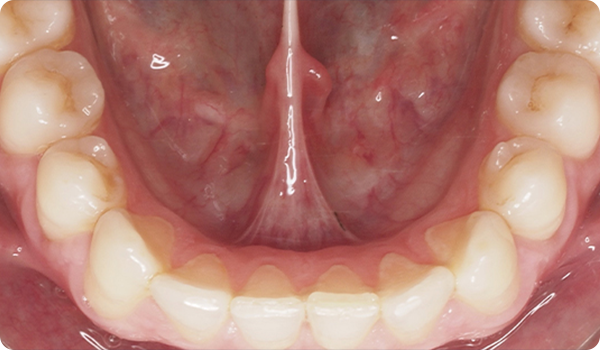

Kliniken skickar tre bilder och STL-filen från en skanning via Corus Link för att utvärdera fallet.

Leenden på plats

Med Right får dina patienter det leende de önskar, inom den tid de vill, på ett bekvämt och ”osynligt” sätt.

Att justera tänder med Right är den perfekta och mest konservativa grunden för framtida blekning eller facettbehandlingar som kommer att föra patientens leende till perfektion.